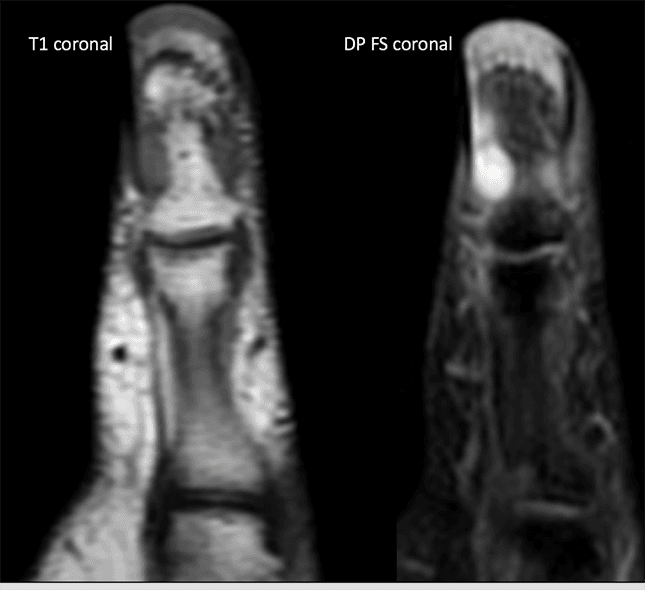

Paciente do sexo feminino, 47 anos, com lesão nodular dolorosa subungueal no I dedo há meses. Relata aumento da sensibilidade nesta região, especialmente no frio.

Imagens